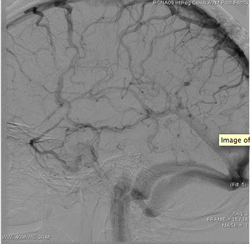

It can be time consuming and laborious to try to determine dynamic information by viewing images available from DSA over and ove

Vascular imaging was revolutionized in the 1980s with the development of DSA. The technique involves injecting a contrast dye into the vascular network while taking a rapid series of X-ray images. The first image, taken before the dye arrives in the field of view, is made into a mask image that is digitally removed, or “subtracted,” from the images showing contrast. The resulting images, which show only the contrast in the vessels, are used to display a 2-D view of the vessels. Because the contrast is traveling through the vessels with the flow of blood, the arteries, capillary circulation, and then the veins are imaged in a DSA series. When used with today’s modern digital flat panel X-ray detectors, DSA produces excellent images of vascular anatomy over time.

But the anatomy of the vessels is only part of the story. Doctors want more information about the patterns and amount of blood flow to make better decisions during image guided interventions. They also want sequential information on a single image, instead of having to scan through a series of DSA images over and over. Finally, they want to see how the flow of blood to an area of tissue has changed as a result of treatment.